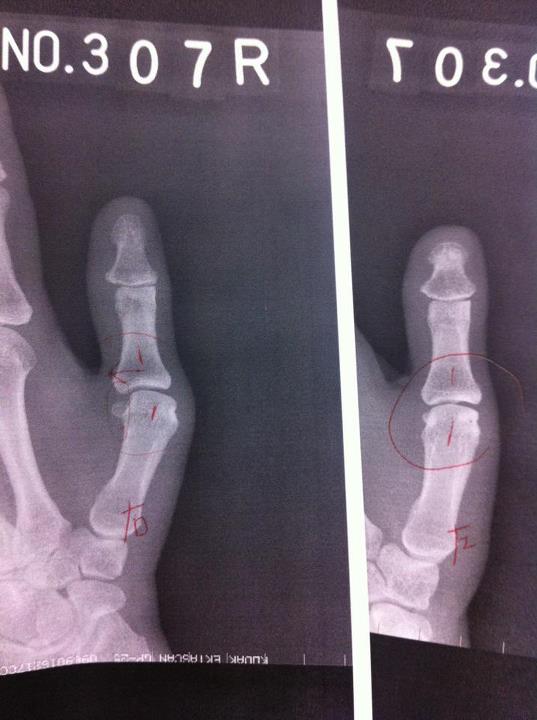

「ほら、ここ。骨ずれてるのわかります?」(写真左)

その後MRI撮ったところ親指内側の靭帯を損傷していて、治すなら手術だと。それはおおごとすぎる・・・。お医者さんも、指をかなり使う職業の人とかでなければ、手術まではしなくても・・・という話だったので、痛みが次第におさまることを期待して、しばらくテーピング固定で様子みることにした。